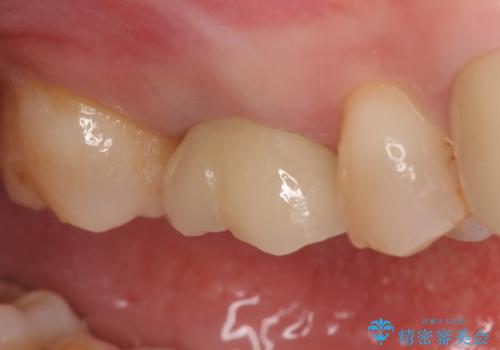

今回用いたオールセラミッククラウンはジルコニアフレームという白い素材の上にセラミックを盛っているため、審美性が非常に高いのが特徴です。

また、ジルコニアは人工ダイヤモンドの材料にも使われているほど高い強度を持っており、そのためオールセラミッククラウンは審美性だけでなく、奥歯やブリッジの補綴も可能とするクラウンです。